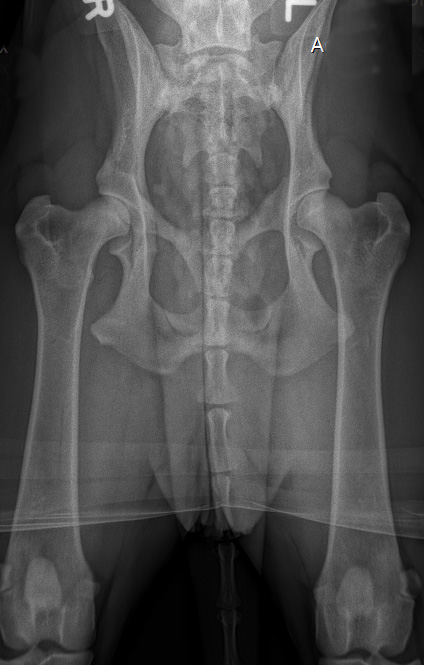

Hier nun einige HD Röntgenbilder:

HD frei / HD- A / HD-0 / HD-normal |

A |

= HD-frei |

HD-0 |

normal |

Normal, unauffällige Gelenke, NORBERG-Winkel von 105 Grad oder mehr |